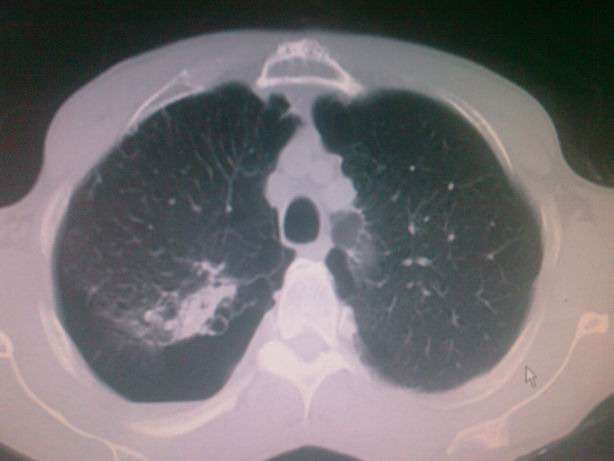

胸片图片肺大泡,肺大泡图片胸片

慢性 支气管炎 伴 肺气肿 ,双肺多发性肺大泡;3.

肺大泡ct肺大疱

肺大泡ct图片

肺大泡ct表现图片

肺大泡ct影像图片

肺大泡ct图片解读